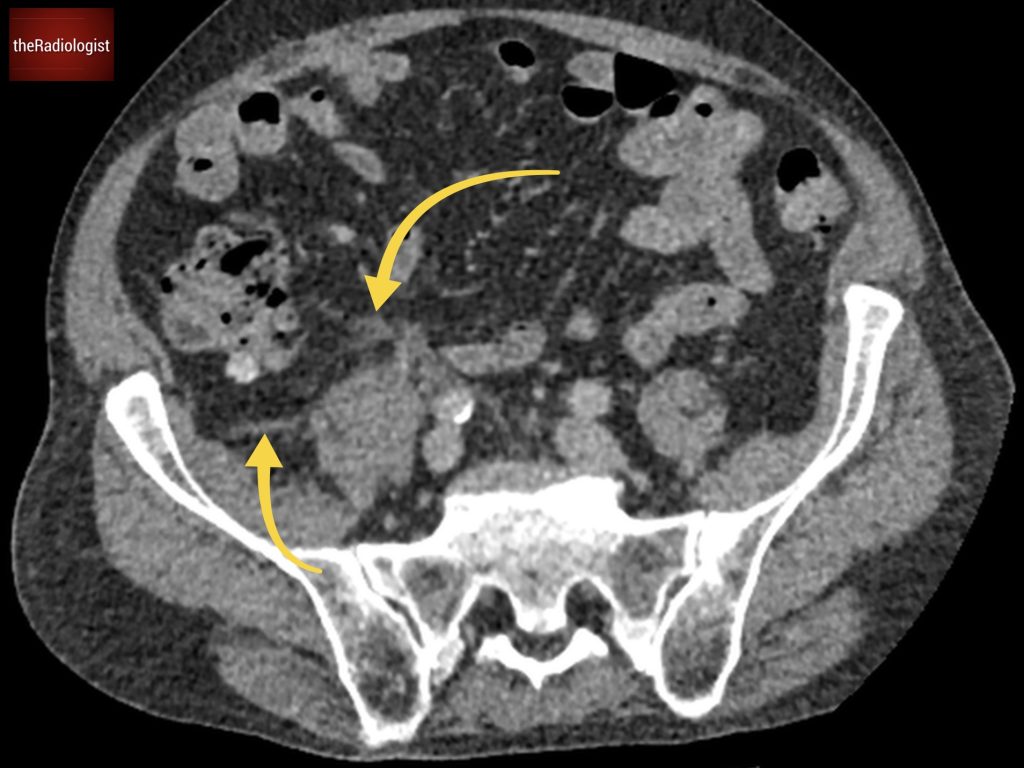

If we look at the psoas muscles on this scan below we can see there is some asymmetry . The right psoas is larger than the left and we’ve lost some of the fat planes within the muscle.

Compare the psoas muscles side by side. The right sided psoas muscle appears expanded with a loss of its normal fat planes.

Also as we scroll down we can see there is fat stranding surrounding the psoas muscle extending into the pelvis.

There is fat stranding surrounding the psoas extending into the pelvis.